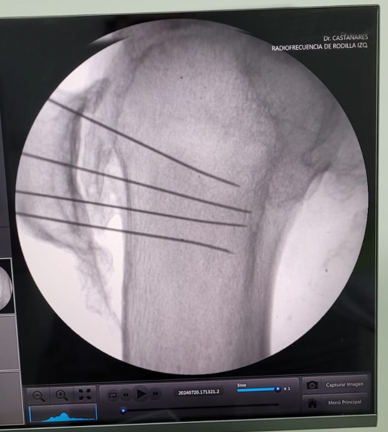

En Tidol tratamos el caso de un paciente de 90 años, con artrosis severa de rodilla izquierda.

El paciente presentaba limitaciones de reemplazo total de rodilla y no se le podía realizar la cirugía por osteoporosis y comorbilidad; por lo que se decidió realizar tratamiento con radiofrecuencia de los nervios geniculados.